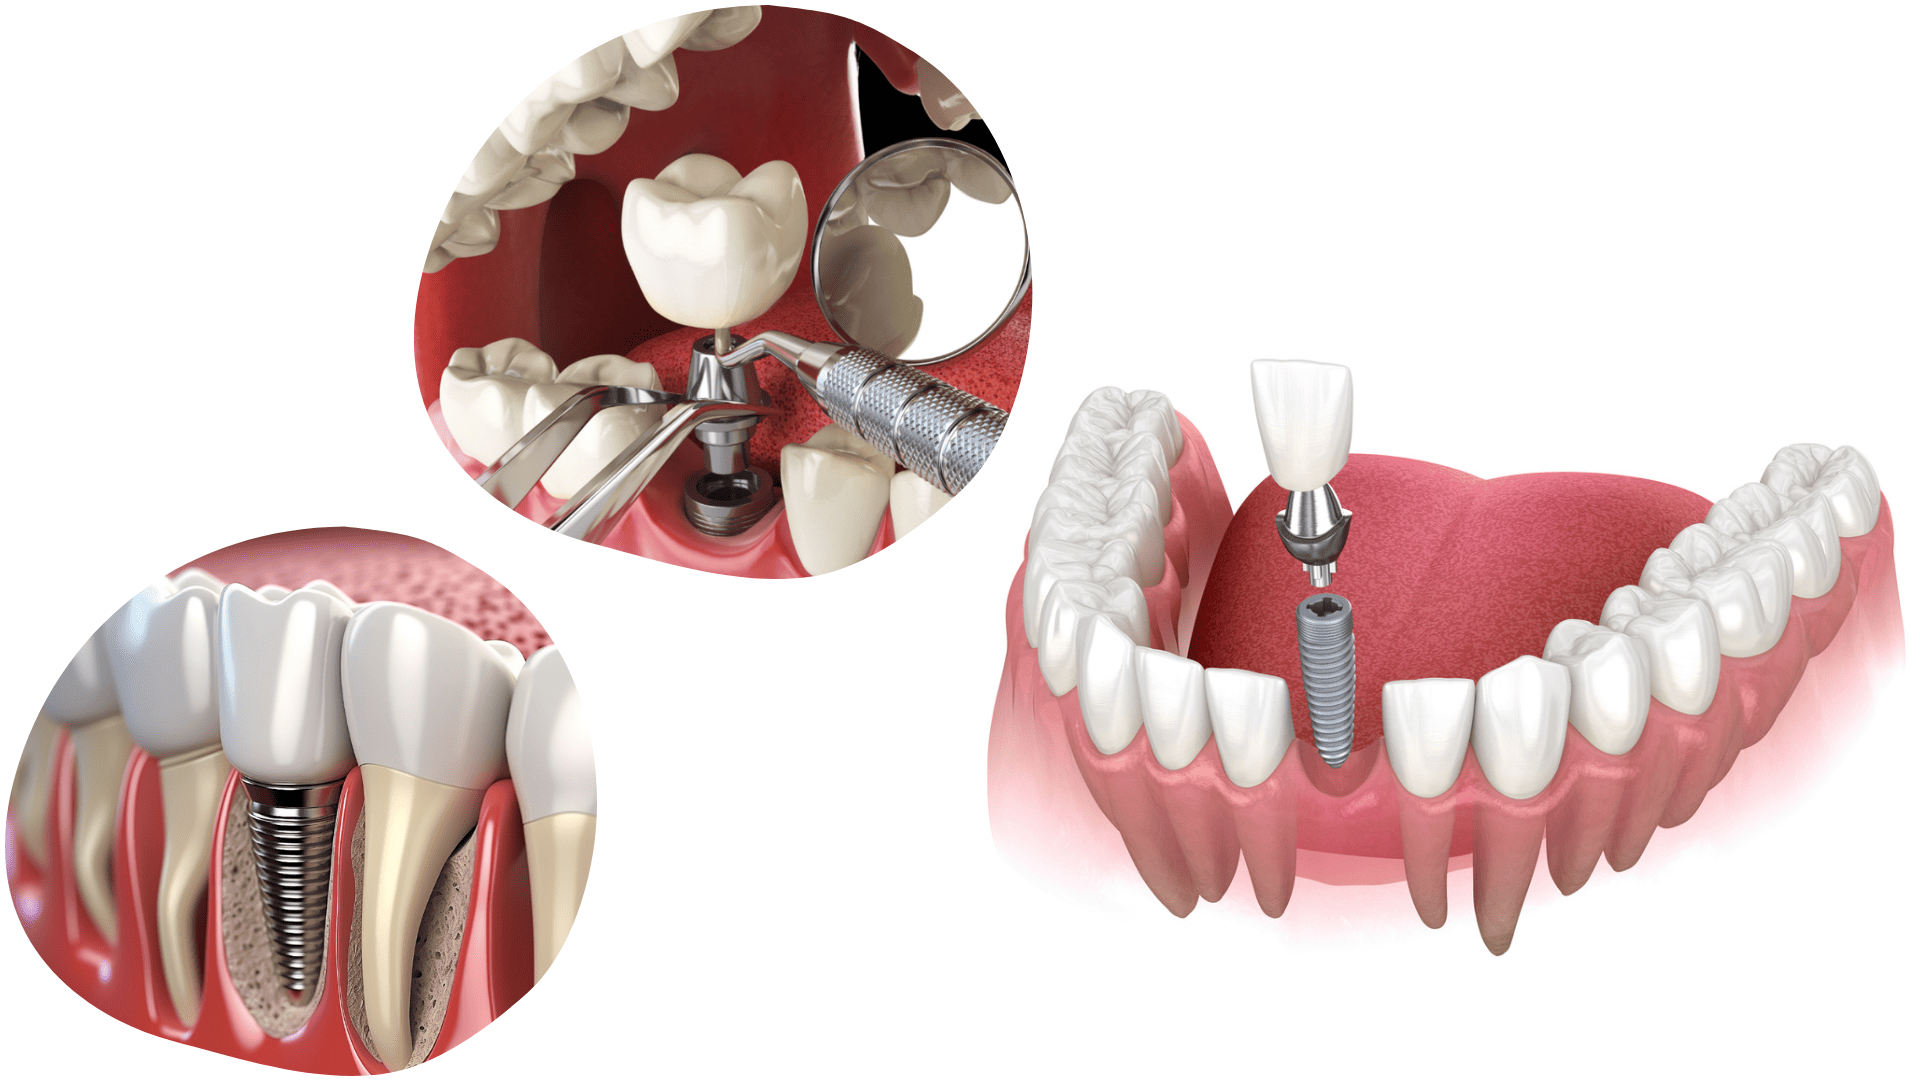

Zubni implantat je titanski vijak koji se ugrađuje u kost i zamjenjuje prirodni korijen zuba te služi kao nosač krunica, mostova i proteza. Titan je biološki neutralan materijal te omogućuje stvaranje čvrste veze između kosti i implantata.

Ugradnju implantata radimo pod lokalnom anestezijom, zahvat je u potpunosti bezbolan i vrlo brz.

Zubnim implantatima rješavamo nedostatak jednog zuba, nekoliko zuba ili svih zuba – potpunu bezubost.

NEDOSTAJE VAM JEDAN ZUB

Nedostatak jednog zuba rješavamo zubnim implantatom sa cirkon keramičkom ili Emax keramičkom krunicom.

NEDOSTAJE VAM VIŠE ZUBA

Nedostatak više zuba u nizu rješavamo potrebnim brojem zubnih implantata i mostom sa cirkon keramičkim ili Emax keramičkim krunicama.

Krunice i mostovi na implatatima su visokokvalitetna i brza fiksna rješenja koja ne uključuju brušenje susjednih

zuba, omogućuju normalan zagriz te pružaju estetiku i funkcionalnost prirodnih zuba.